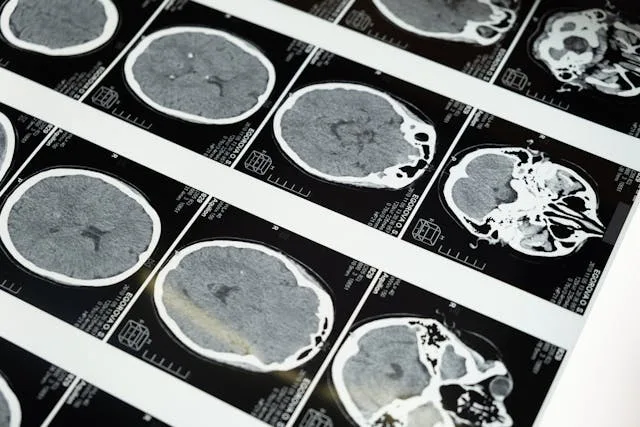

CT skener, poznat i kao multislajsni skener (MSCT), predstavlja savremenu dijagnostičku metodu koja koristi kontrolisanu dozu jonizujućeg zračenja i napredne softverske algoritme za dobijanje detaljnih, slojevitih prikaza unutrašnjih organa i struktura tela.

Za razliku od klasičnog rendgena, CT skener omogućava trodimenzionalni prikaz organa i tkiva, što ga čini izuzetno važnim u preciznoj i brzoj dijagnostici.

Visoka rezolucija slike

Trodimenzionalni prikaz

Tokom pregleda pacijent leži na pokretnoj platformi koja prolazi kroz CT aparat. Snimanje traje svega nekoliko minuta. U nekim slučajevima koristi se kontrastno sredstvo radi detaljnijeg prikaza struktura.